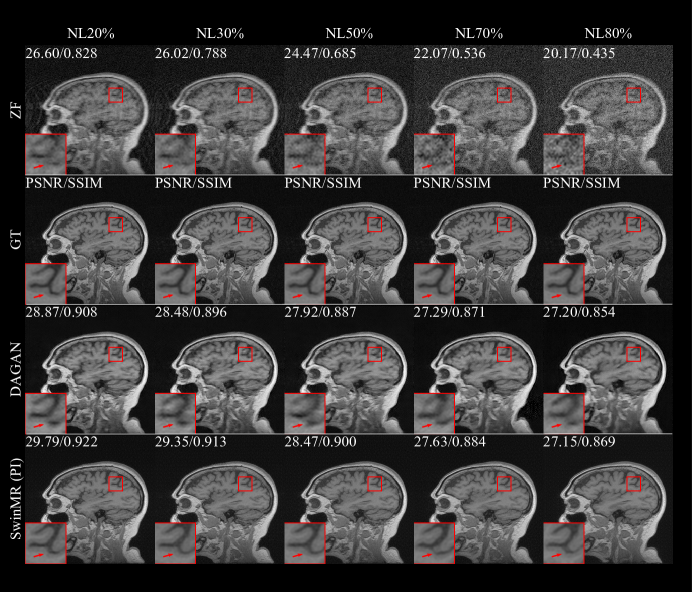

The quantitative results of the noise experiments are shown in Figure 9 and Table 3. The sample of reconstructed images, edge information and absolute differences of standardised pixel intensities (10×10\times) between reconstructed images and GT images are shown in Figure 10, Figure 11 and Figure 12, respectively.

According to the results, under the interruption of noise, SwinMR maintains better reconstruction quality compared to DAGAN. The quality improvement becomes more clear when under a high noise level.

Figure 10: Samples of the experiment on different noise using Gaussian 1D 30% mask. Five noise levels (NL20%, NL30%, NL50%, NL70% and NL80%) were tested in this experiment. Row 1: Undersampled zero-filled MR images (ZF) with different noise levels; Row 2: Ground truth MR images (GT); Row 3: Reconstructed MR images by DAGAN; Row 4: Reconstructed MR images by SwinMR (PI). The Peak signal-to-noise ratio (PSNR) and Structural similarity index (SSIM) of reconstructed and ZF images are shown in the top-left corner.